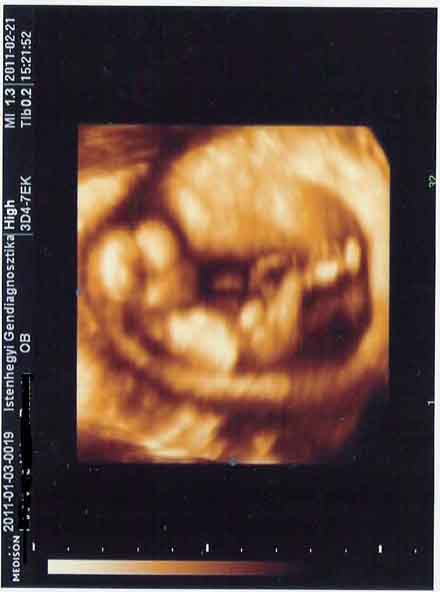

legkozelebb marcius 4en van ultrahangom, addig meg gyozkodom uramat, h menjunk itt el 4D-re. irigykedve nezem a fotoitokat!!! itt kepzeljetek nem divat a 4D, csak a 6ik honap korul, a korhaz ahova tartoznak a kismamak, ingyen, ugymond ajandekba megcsinaljak. de ez inkabb gesztus, emlek, mint nem-megallapitas.

privat helyen, ugy, mint otthon szinten meg lehet csinalni, de eleg draga kb 150 euro...

en mar annyira kivancsi vagyok pedig!!! na, most el is dontottem, h elmegyunk!!